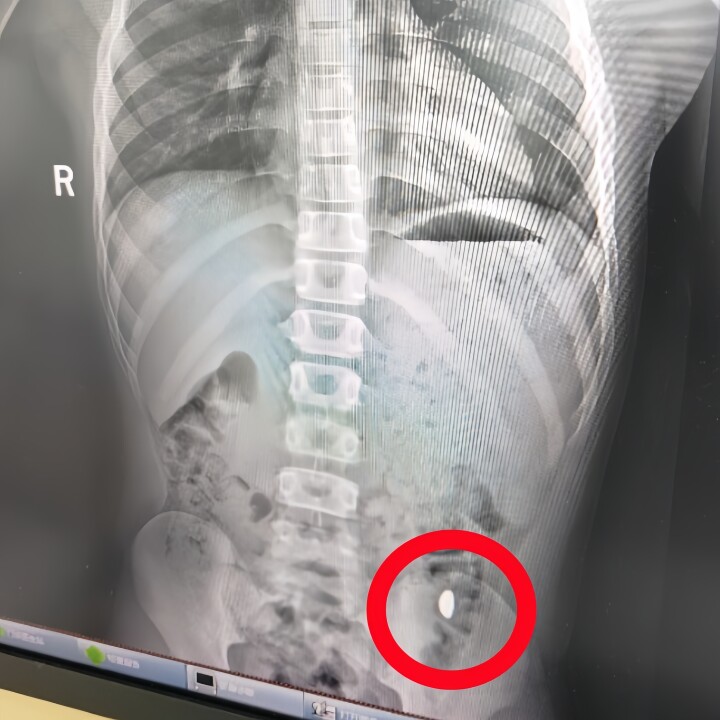

昆山市第5人民医院の医師が息子を診察し、レントゲン写真を撮影したところ、胃の中に金の粒と見られる「異物」が見つかった。そして、病院から帰ったその日の午後、息子の大便からついに金の粒が出てきたとのことだ。